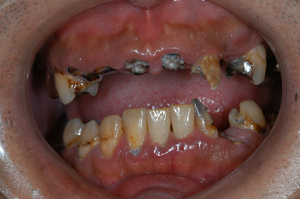

糖尿病内科の患者様を紹介されることが多くなりました。(当院では1回歯周病治療を行っているので)糖尿病は自覚症状が出にくいため、糖尿病と診断されても、治療を受けない人、治療を中断する人が

およそ50%に及ぶそうです。そのまま放置すると、動脈硬化・脳梗塞・神経疾患・腎臓病・失明・認知症

足の壊疽などの合併症のリスクが高まります。

歯周病も糖尿病の合併症の1つと言われていて、深い関連性があります。

歯周病で歯ぐきに出血・炎症・膿があると、化学物質が血管を経由して血糖値を下げるインシュリンの働きを阻害します。

その結果、糖尿病になります。

歯周病を改善することは、歯をキレイにすることだけでなく、様々な合併症のリスクを抑制して、健康な体を取り戻します。